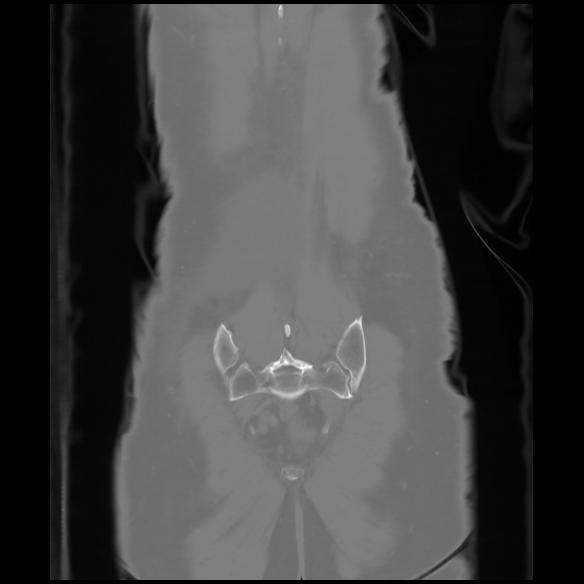

6 CUERPO,CE,Coronal,3.000,CUERPO,Coronal,